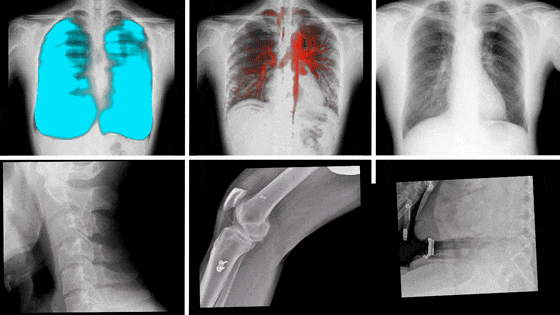

动态DR影像

随着科学技术的不断发展,动态DR在未来还将拥有更多的发展空间,在更多领域得到应用,如儿科、骨科、呼吸科等,为更多患者提供高质量的医疗服务。